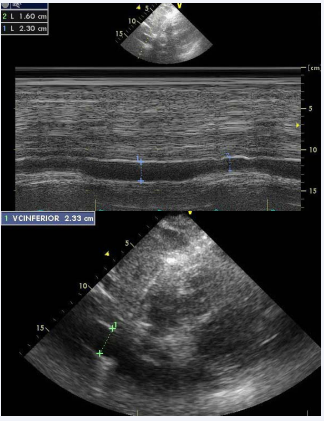

Inferior Vena Cava Dimension

The subcostal view allows imaging and measurement of the IVC and assesses inspiratory collapsibility too. IVC diameter should be evaluated just proximal to the proximal of hepatic veins (Figure 4).

Figure 4: Measure of IVC (Subcostal view).

For simplicity and kinship of reporting, values of RA pressure, instead of ranges, should be used in the stabilizationof pulmonary artery pressure. IVC diameter 2.1 cm that collapses > 50% with a sniff suggests normal RA pressure of 3mm Hg (range, 0-5mm Hg), while IVC diameter > 2.1 cm that collapses < 50% with a sniff suggests high RA pressure of 15mm Hg (range, 10- 20mm Hg). IVC diameter and collapse do not fit this paradigm, an intermediate value of 8mm Hg (range,5-10mm Hg) may be used or,favourably, other indices of RA pressure should be compounded to downgrade or upgrade to the normal or high values of RA pressure [1].